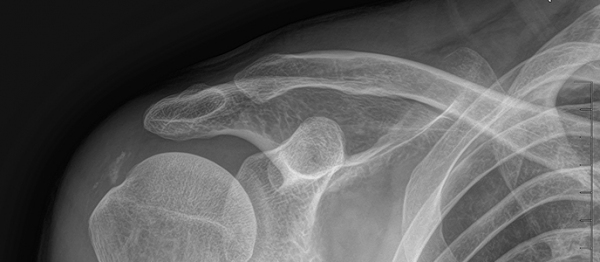

석회쇄석흡인술 페이지 정보 작성자최고관리자 등록일 2025-02-26 17:16 조회22 본문 치료 증상 갑자기 팔 들기 힘듦, 밤에 아픔 나이 / 성별 55세 / 남성 치료내용 석회쇄석흡인술 후 호전 치료기간 2024-11-22 ~ 2025-02-22 null 목록 다음글석회쇄석흡인술 25.02.25 댓글 0 댓글목록 등록된 댓글이 없습니다.